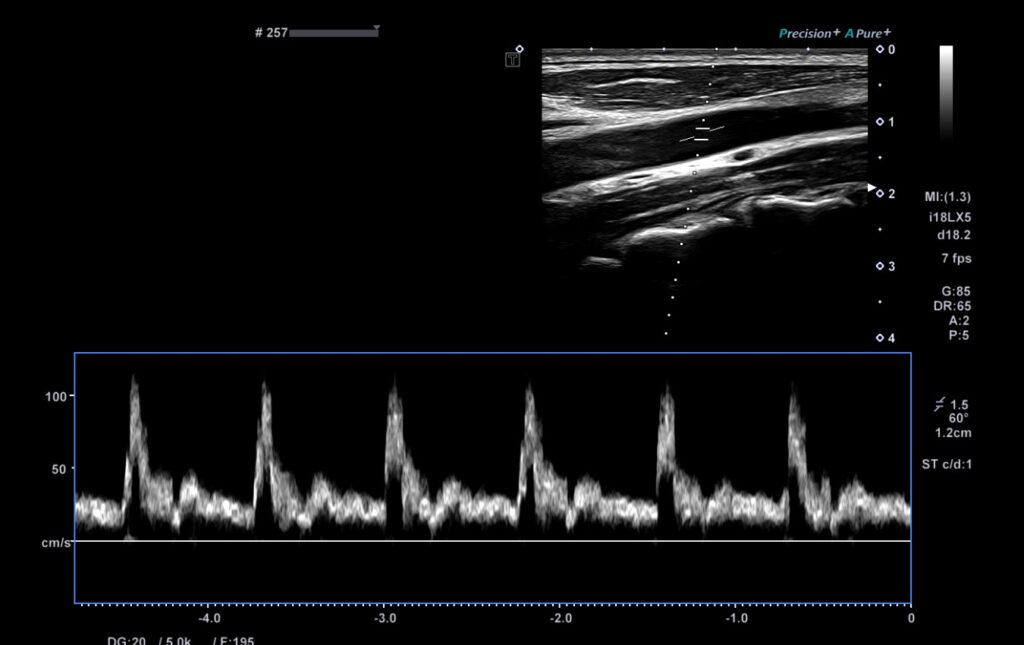

Через минуту данные пошли на экран.

— Левая PCA, фазовый сдвиг?

— 0.62, — ответил техник.

— Правая?

— 1.14.

— А RoR справа?

— 29.8.

— Вот и всё, — сказал профессор.

Он бросил взгляд на распечатку кросс-спектрального анализа, где в одной из отведённых пауз был почти незаметный сдвиг. Он вспомнил зрачки пациента — чуть медленнее справа. Тогда он понял, что дело не в психике.

Суть клинического случая: Мужчина 34 лет поступает с жалобами на головную боль и ощущение «тумана» в голове. Все стандартные обследования (КТ, анализы) — в норме. Коллеги подозревают психосоматику или симуляцию. Однако профессор находит тонкие неврологические признаки и проводит двустороннее ТКД-исследование с кросс-спектральным анализом, выявляя асимметрию фазового сдвига (;PS) и снижение RoR, указывающие на сосудистую проблему.